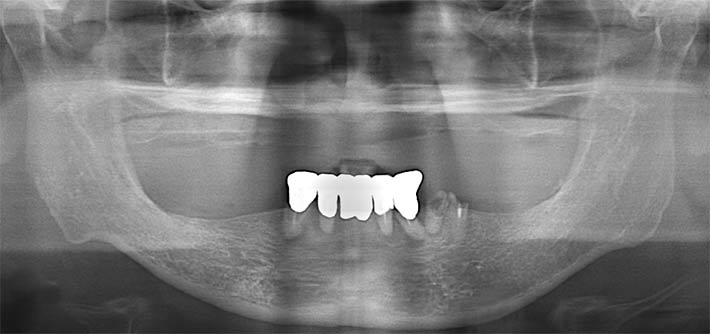

パノラマX線

上顎:合わない義歯を長期に使用していた為、歯槽骨がかなり失われている事がわかる。

下顎:通常のオールオン4治療が出来る。